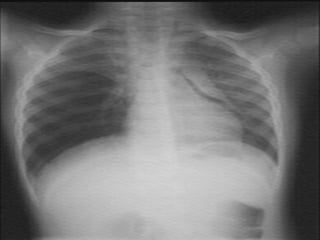

a- RX du thorax :

 clichés de face et de profil en inspiration profonde.

 RX de thorax de face en expiration forcée un  :

● épanchements minimes.

● La surveillance évolutive :total retour

du poumon à la paroi.

 Apports :

 Affirmer le pneumothorax.

 Définir le caractère complet ou incomplet du

pneumothorax

 Estimer la taille de l’épanchement.

 Analyser le parenchyme pulmonaire sous-jacent

et du coté opposé.

 Suivre l’évolution : retour du poumon à la paroi.